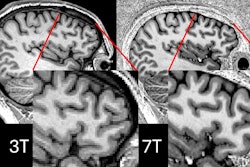

Functional MRI (fMRI) is further revealing changes in the brain caused by repetitive blast exposure and highlights the need to rethink "mild" brain injuries across society, according to research published April 1 in Radiology.

A team led by neuroradiologist Andrea Diociasi, MD, from Mass General Brigham in Boston studied 220 U.S. military special operations forces members and found that when standard MRI exams appeared normal, resting-state fMRI maps obtained from functional connectivity (FC) multivariate patterns analysis, along with volumetric analysis, showed distinct differences between brain regions of interest, depending on blast exposure.